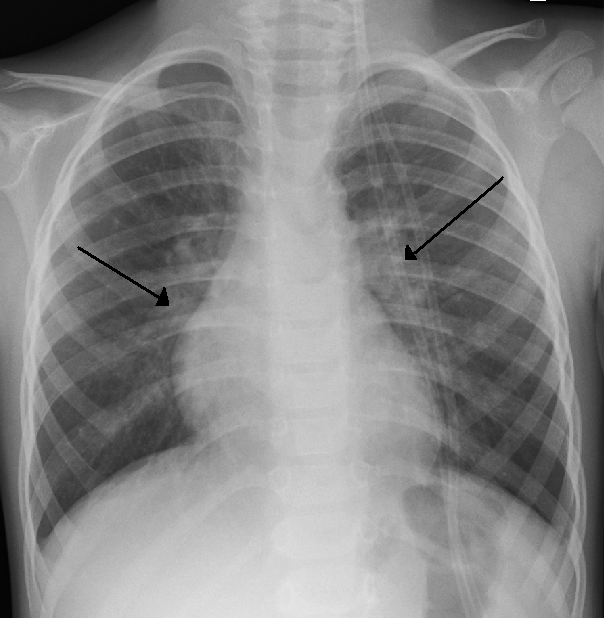

Neoplasias Pulmonares

La tele de tórax es una herramienta útil para la detección temprana de cáncer de pulmón, especialmente en pacientes con factores de riesgo como el tabaquismo o antecedentes familiares. En las radiografías, los tumores pulmonares se presentan como masas o nódulos. Aunque una biopsia es necesaria para confirmar el diagnóstico, la radiografía de tórax puede alertar al médico sobre la posible presencia de un tumor.

La tele de tórax es una herramienta útil para la detección temprana de cáncer de pulmón, especialmente en pacientes con factores de riesgo como el tabaquismo o antecedentes familiares. En las radiografías, los tumores pulmonares se presentan como masas o nódulos. Aunque una biopsia es necesaria para confirmar el diagnóstico, la radiografía de tórax puede alertar al médico sobre la posible presencia de un tumor.

Caso Clínico:

Un paciente fumador crónico con tos persistente y pérdida de peso fue evaluado mediante una tele de tórax. La radiografía reveló un nódulo pulmonar en el lóbulo superior derecho, lo que llevó a realizar más pruebas y finalmente a diagnosticar un cáncer de pulmón en etapa temprana.